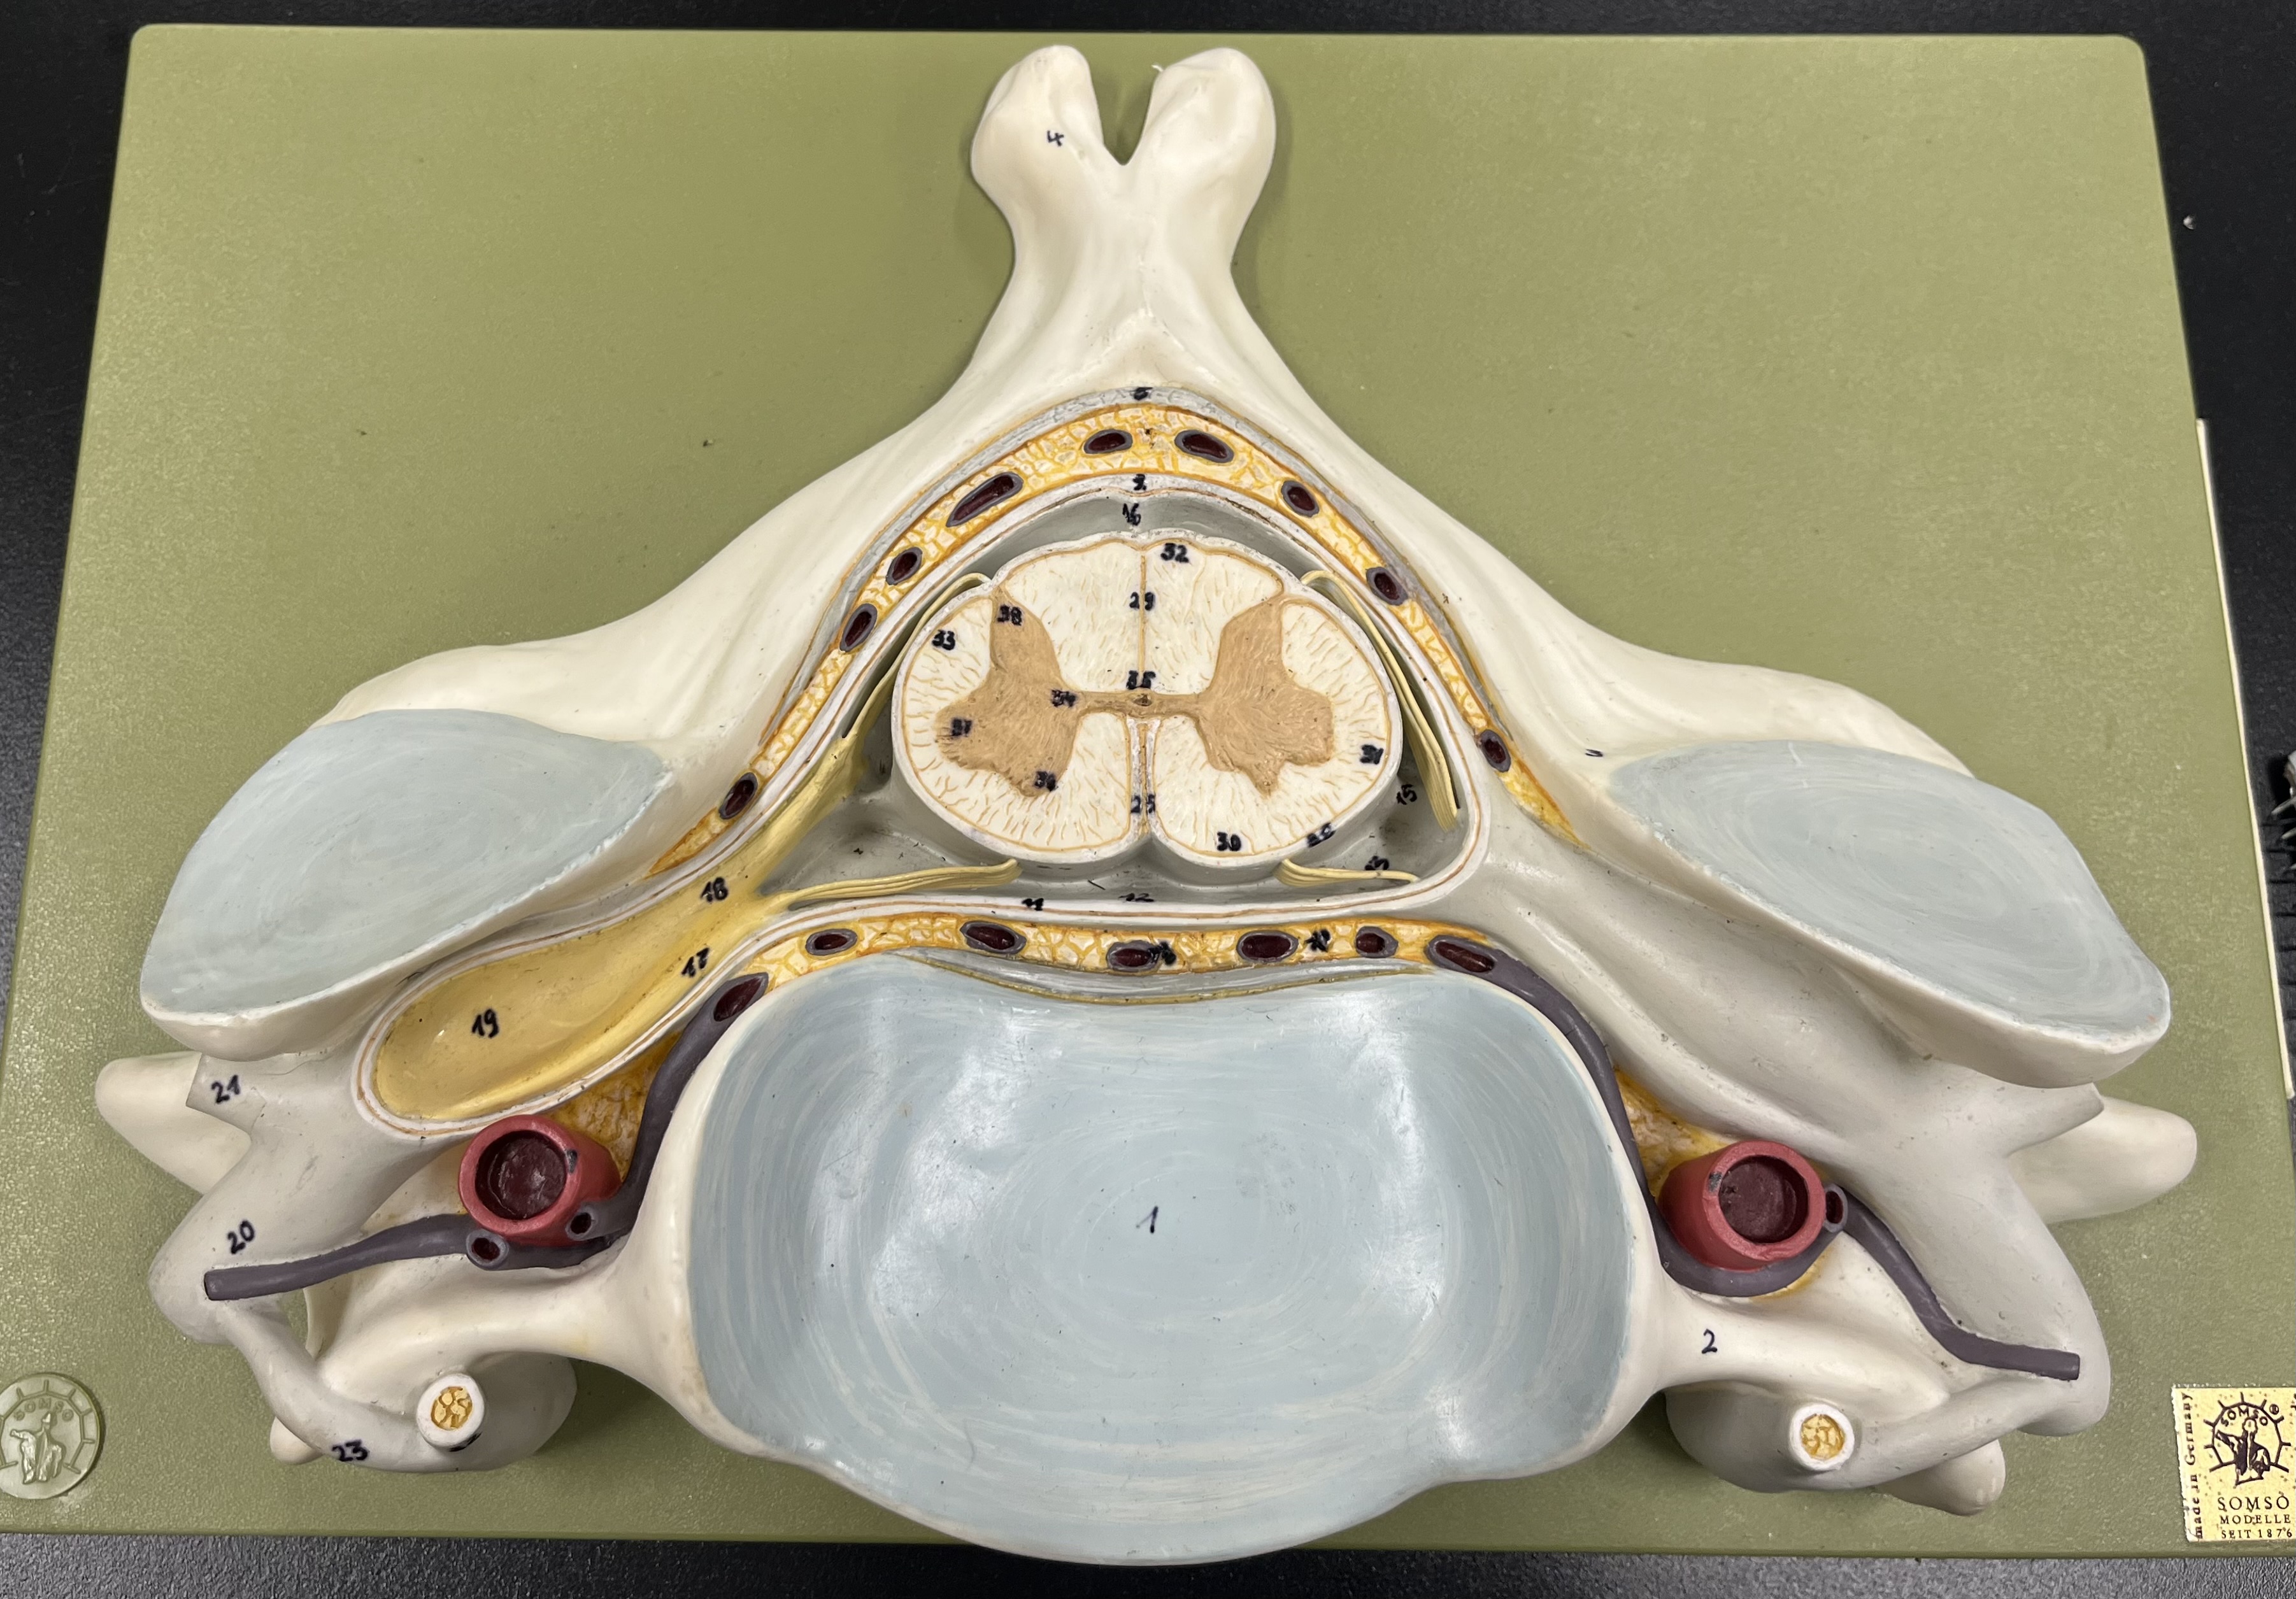

epidural space

dura mater

subdural space

arachnoid mater

subarachnoid space

pia mater

denticulate ligaments

What is the groove here?

anterior median fissure

posterior median sulcus

posterior (dorsal) horn

posterior (dorsal) horn; R—>L

anterior (ventral) horn

lateral horn (selected models)

gray commissure

central canal

anterior column

lateral column

posterior column

white commissure

posterior (dorsal) root ganglion

What is the bulb here?

posterior (dorsal) root ganglion

posterior (dorsal) root

posterior (dorsal) root

anterior (ventral) root

anterior (ventral) root

dorsal ramus

dorsal ramus

ventral ramus

ventral ramus

rami communicantes

rami communicantes

sympathetic chain ganglia

sympathetic chain ganglia